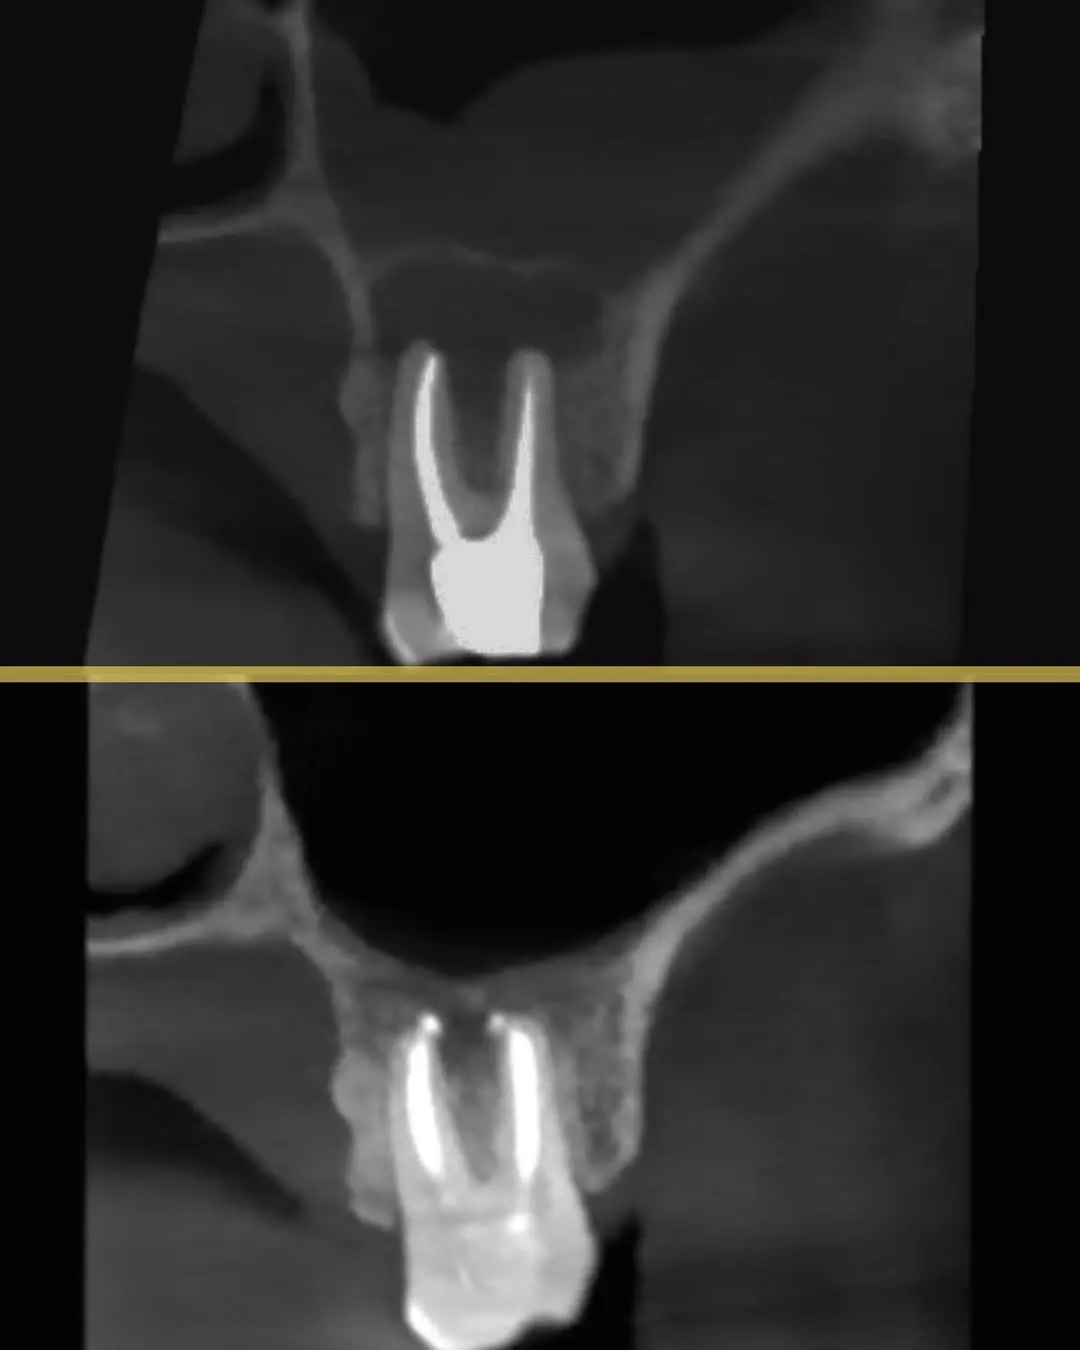

يقود رحلة علاج الجذور داخل مركبة كلاس بخبرة ودقة عالية مع تركيز على إنقاذ الأسنان الطبيعية كلما كان ذلك ممكناً. يمتلك أكثر من 10 سنوات خبرة سريرية ومخصص في حالات حشوات الجذور المعقدة وكذلك مشاكل تآكل العظم. يعتمد على التشخيص المتقدم والتقنيات الحديثة للوصول إلى أدق تفاصيل الجذور ومعالجتها بكفاءة عالية مع ضمان تجربة علاج مريحة وأمنة للمريض ومتابعة دقيقة للحصول على أفضل النتائج واستعادة الراحة والوظيفة الطبيعية للأسنان. بالإضافة إلى خبرته العملية هو متحدث دولي في مجال علاج الجذور ومتحدث رسمي لشركات عالمية مرموقة مثل Woodpecker وOrikam وMDcluss، ما يعكس مستوى عالمي من المهارة والمعرفة التي يقدمها في كل عالج.

نتائج حالات د. اثير عدنان